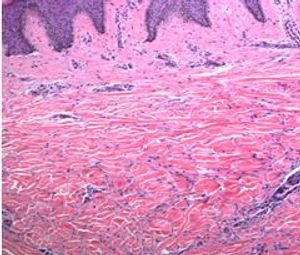

This relatively uncommon inflammatory dermal process has previously been associated with diabetes mellitus and more recently with hyperlipidemia.